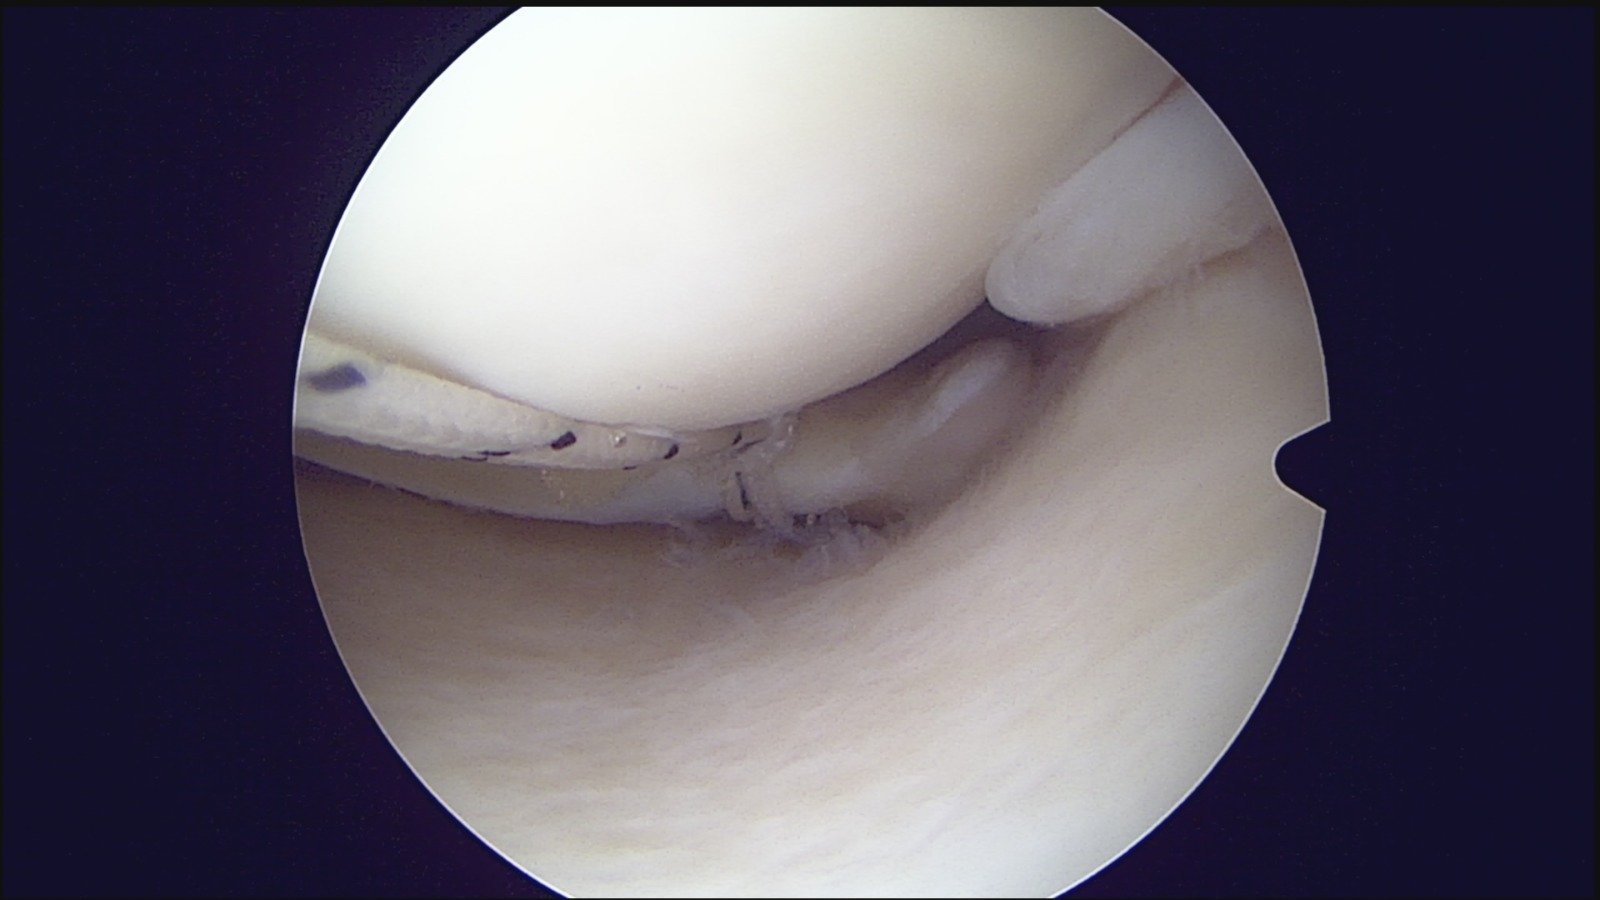

GalleryShoulder rotator cuff repair Meniscus root repair Meniscus repair Bankart repair for recurrent shoulder dislocation ACL reconstruction Machines Instruments